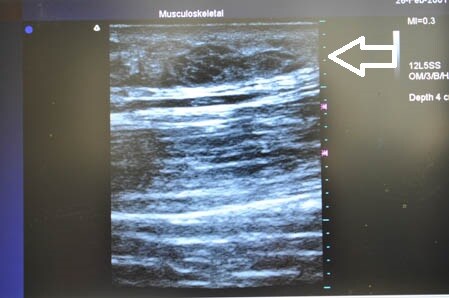

いつものように3Dタッチビューから。

白い矢印部分が皮下脂肪層です。

右の太もも後面です。

上の画像部分をつまんでみましょう。